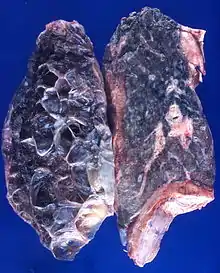

Left lung completely affected by bullae shown in contrast to a normal lung on the right.

In the lungs, emphysema involves enlargement of the distal airspaces,[2] and is a major feature of chronic obstructive pulmonary disease (COPD). Other pneumatoses in the lungs are focal (localized) blebs and bullae, pulmonary cysts and cavities.